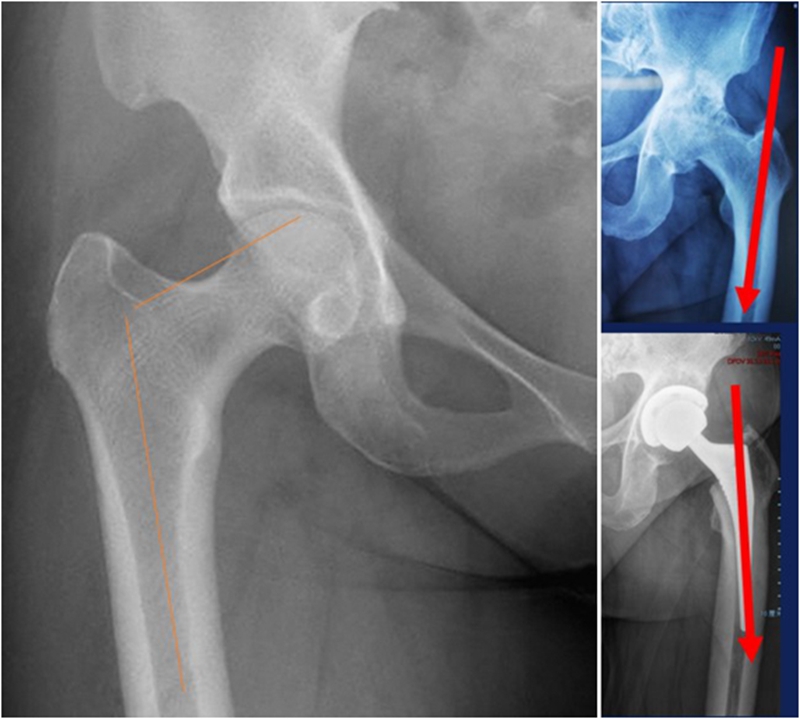

Ⅱ、股骨颈畸形---髋内外翻,offset异常

(1)颈干角偏小(<120°)——髋内翻

髋内翻,颈干角小,偏心距较大,选择high-Offset假体,以维持外展肌张力。

(2)颈干角过大(>140°) ——髋外翻

髋外翻多见于DDH,难度在于股骨距内侧皮质阻挡假体完全坐入髓腔,强行打击造成股骨距骨折。

Ⅲ、干骺端畸形

硬化骨、骨赘、骨质疏松、髓腔宽大

转子间骨折畸形愈合后常导致干骺端畸形,干骺端遗留大量硬化骨或髓腔成角,术中需在确认髓腔开口位置后,首选用小骨刀或高速磨钻去除硬化骨,打通髓腔。